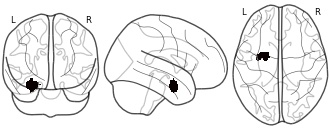

License information was derived automaticallyDescriptionConnectivity-based parcellation (CBP) of the left human amygdala. Cluster #3 (blue) - laterobasal nuclei group

We here employed methods for large-scale data mining to perform a connectivity-derived parcellation of the human amygdala based on whole-brain coactivation patterns computed for each seed voxel. Using this approach, connectivity-based parcellation divided the amygdala into three distinct clusters that are highly consistent with earlier microstructural distinctions. Meta-analytic connectivity modelling and functional characterization further revealed that the amygdala's laterobasal nuclei group was associated with coordinating high-level sensory input, whereas its centromedial nuclei group was linked to mediating attentional, vegetative, and motor responses. The results of this model-free approach support the concordance of structural, connectional, and functional organization in the human amygdala. This dataset was automatically imported from the ANIMA <http://anima.modelgui.org/> database. Version: 1